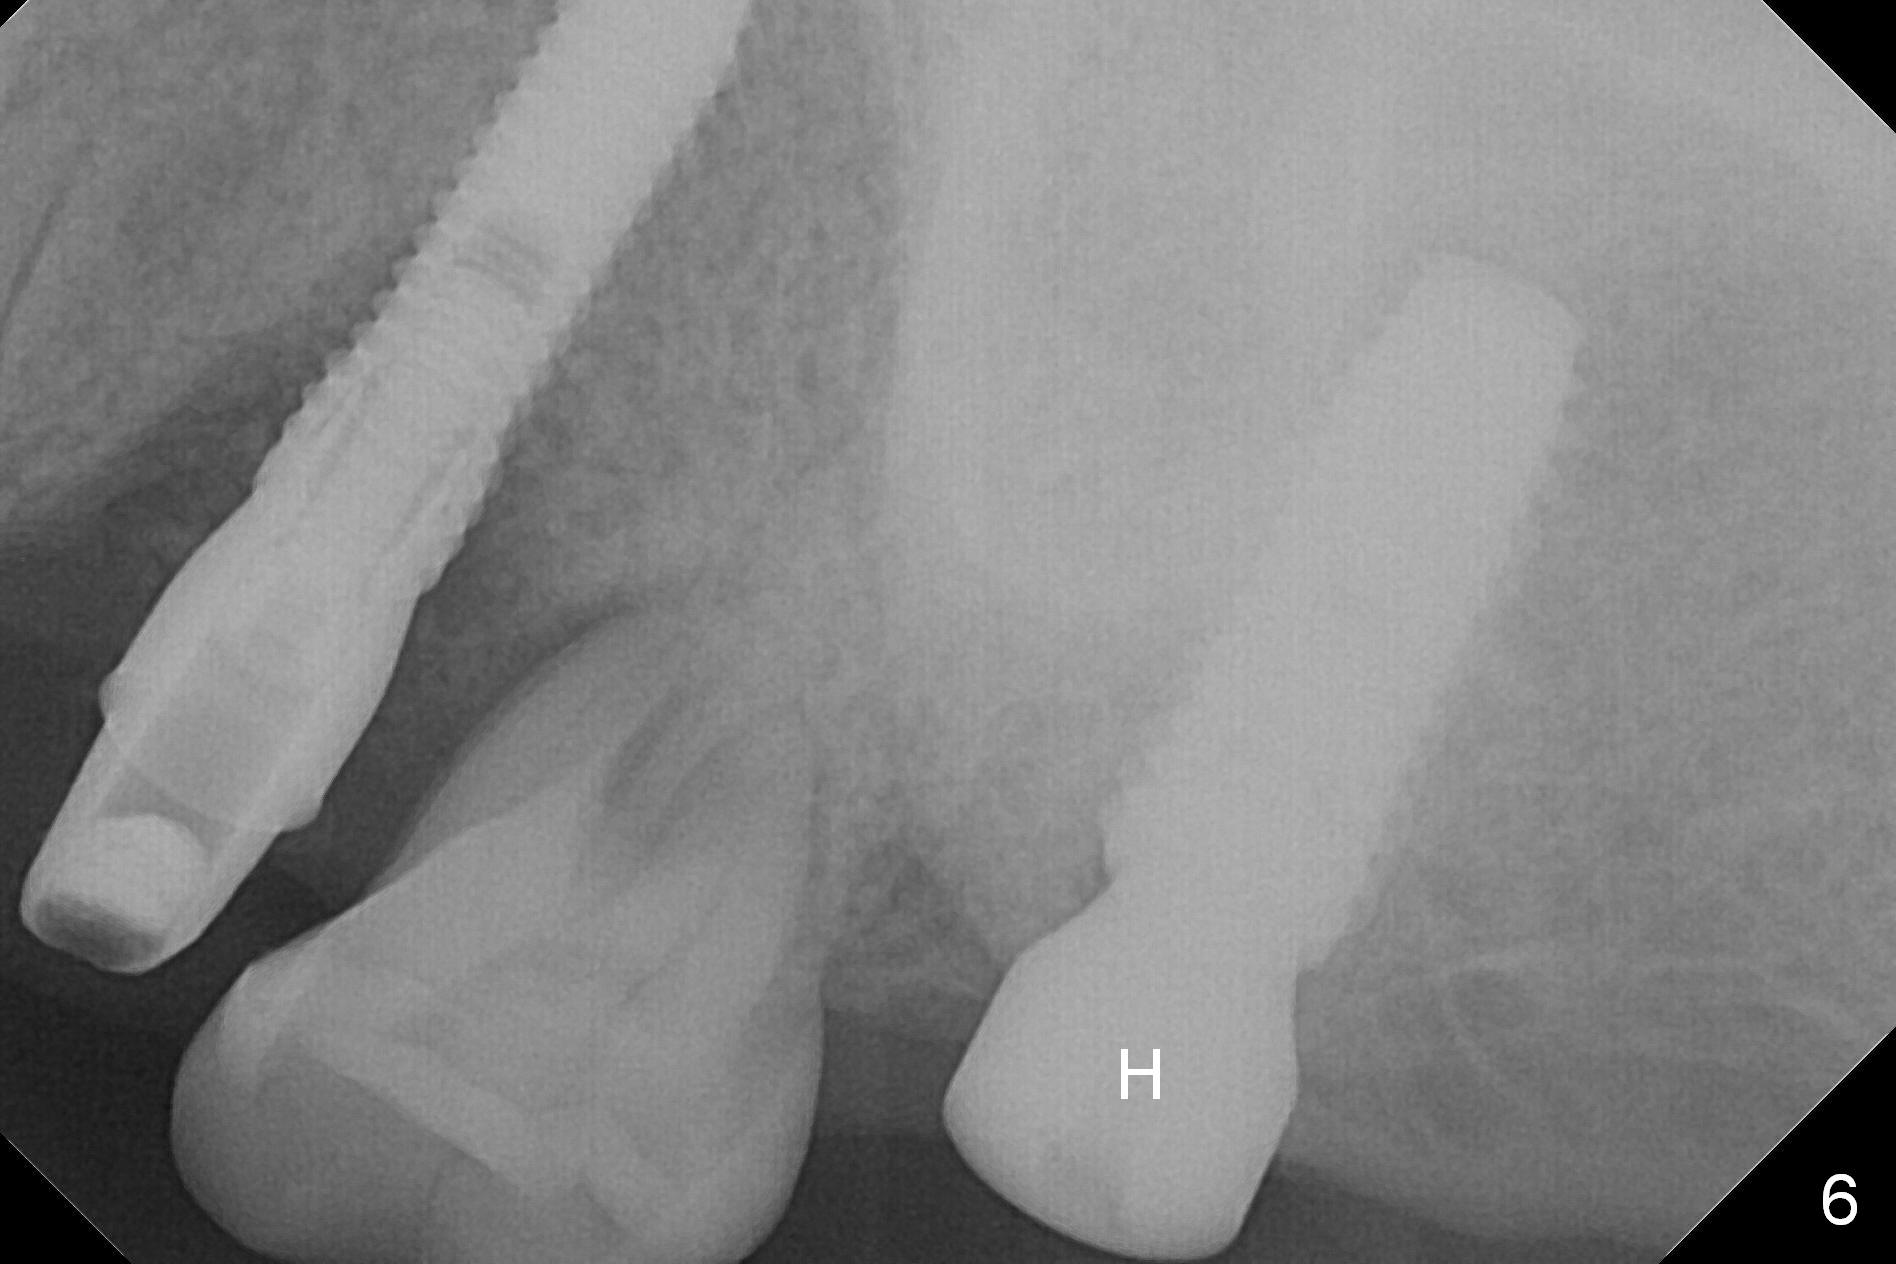

A 1.2 mm initial drill is used to start osteotomy at the site of #15 (Fig.1). After moving the osteotomy distally (with Lindamann bur), the osteotomy is enlarged by DIO Bone Expanders until 2.4/3.7 mm for 18 mm (gingival level) (Fig.2). Following the expander 3.0/4.4 mm, a 5x13 mm UF implant is placed supracrestal (Fig.3,4). After deepening the osteotomy with 3.8 mm drill for 3 mm, the implant is placed deeper by ~ 2 mm (Fig.5 arrow). Since the tooth #18 is supraerupted, a healing abutment (5.5x12(3) mm) is placed (Fig.6: H); the gingiva adapts to the abutment well. Suture is not necessary. The bone remains stable 2 and 4.5 months postop (Fig.7,8). Impression is taken. A crown is delivered nearly 6 months postop (08/07/2017). While there is minimal bone loss at #13 and 15 three years and 4 months post cementation, the tooth #14 and 18 are mobile (Fig.13,14, #13).